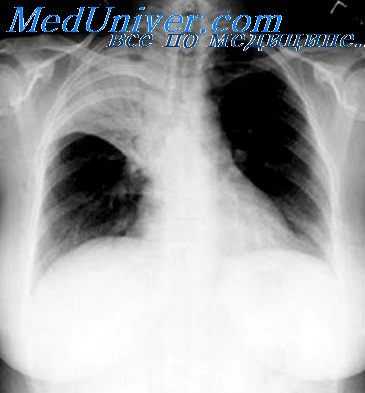

Проводится тщательное рентгенологическое обследование (рентгенография грудной клетки, томография, рентгенография пищевода, пневмомедиастинография). Рентгенологически при медиастините может выявляться расширение тени шеи и средостения, эмфизема средостения, пневмоторакс, гидроторакс, уровень жидкости в средостении, пищеводные свищи.

- Лучевая диагностика. Обязательным методом обследования при подозрении на пневмомедиастинум является рентгенография грудной клетки в двух проекциях. На рентгеновских снимках определяются полосы газа, подчёркнута медиастинальная плевра, чётко очерчены контуры средостения. Анализ рентгенограмм в динамике позволяет выявить нарастание эмфиземы. В неясных случаях показана КТ грудной полости.